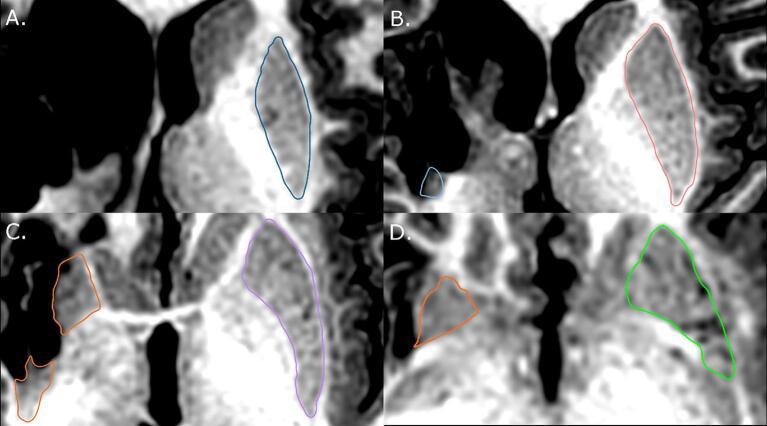

Children with AIS or PVI, and controls, aged 6-19 years, were recruited from a population-based cohort. MRIs were acquired on a 3 T GE MR750w scanner. High-resolution T1-weighted images (166 slices, 1 mm isotropic voxels) underwent manual segmentations of bilateral caudate and putamen. Extracted volumes were corrected for total intracranial volume. A structure volume ratio quantified hemispheric asymmetry of caudate and putamen (non-dominant/dominant hemisphere structure volume) with ratios closer to 1 reflecting a greater degree of symmetry between structures. Participants were additionally dichotomized by volume ratios into two groups, those with values above the group mean (0.8) and those below. Motor function was assessed using the Assisting Hand Assessment (AHA) and the Box and Blocks test in affected (BBTA) and unaffected (BBTU) hands. Group differences in volumes were explored using Kruskal-Wallis tests, and interhemispheric differences using Wilcoxon. Partial Spearman correlations explored associations between volumes and motor function (factoring out age, and whole-brain white matter volume, a proxy for lesion extent).

我们从一个基于人群的队列中招募了患有 AIS 或 PVI 的儿童和对照组,年龄在 6-19 岁之间。使用 3T GE MR750w 扫描仪进行 MRI 采集。高分辨率 T1 加权图像(166 个切片,1mm 各向同性体素)对双侧尾状核和壳核进行手动分割。提取的体积经过校正,以补偿总颅内体积。结构体积比量化了尾状核和壳核的半球不对称性(非优势/优势半球结构体积),比值越接近 1,表明结构之间的对称性越大。参与者还根据体积比分为两组,即大于组平均值(0.8)和小于组平均值的两组。使用辅助手评估(AHA)和患侧(BBTA)和健侧(BBTU)手的盒式积木测试评估运动功能。使用 Kruskal-Wallis 检验探索组间体积差异,使用 Wilcoxon 检验探索半脑间差异。偏 Spearman 相关分析探索了体积与运动功能之间的关联(考虑了年龄和全脑白质体积,这是病变程度的替代指标)。